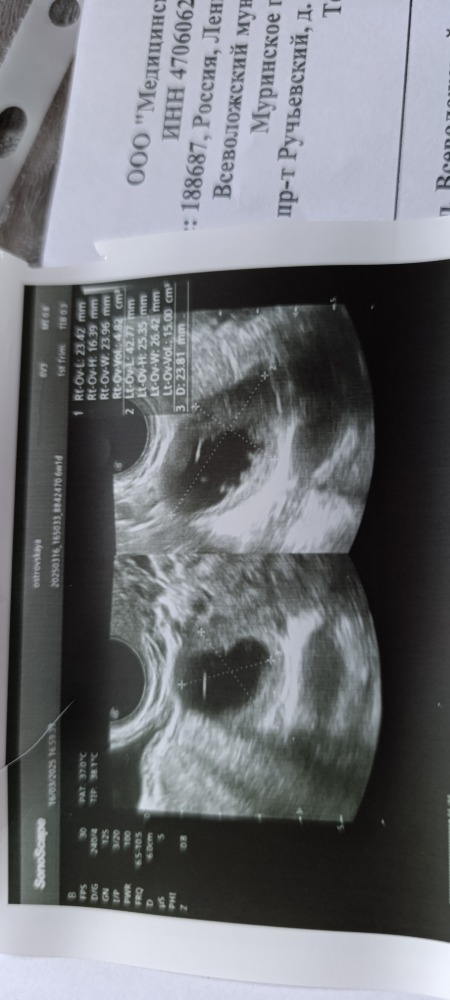

Узи 6,1 недели, плодное яйцо есть, но нет эмбриона. Размер плодного яйца не написан, написано сдм (что это?) 13 мм, желточный мешочек 3,2 мм. ХГЧ не сдавала, завтра пойду и через 48 часов. Я сколько читала и шла уже услышать сб+

У меня на 6 неделях было ПЯ 14 мм, желточный мешок 2,7 (вроде), эмбриона не было. На 7 неделях ПЯ 25 мм, ЖМ 3 (кажется, уже не помню), КТР 9 мм, СБ +. Смотрите УЗИ в динамике, шансы еще есть)